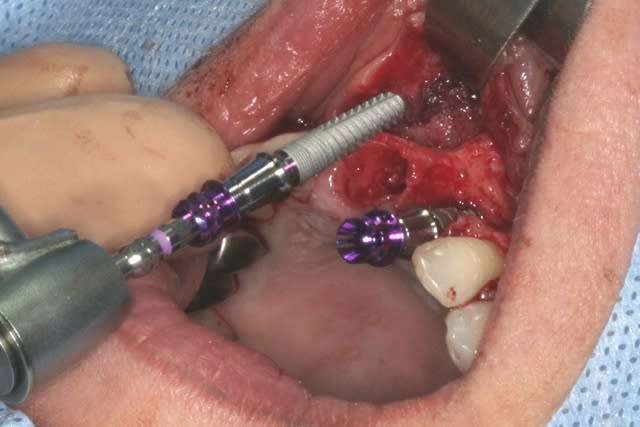

cet implant est une merveille!!!

connexion au top, pièces prothétiques aussi, facilité de pose incroyable...

tien, ce matin, extraction de 24/25, curetage méticuleux, forage, comblement du gap, pose des 2 implants qui se sont bloqués à 50Ncm au CA sur les 3 ou 4 mm apicaux, pose des vis de cicat, sutures...35min....tranquille...